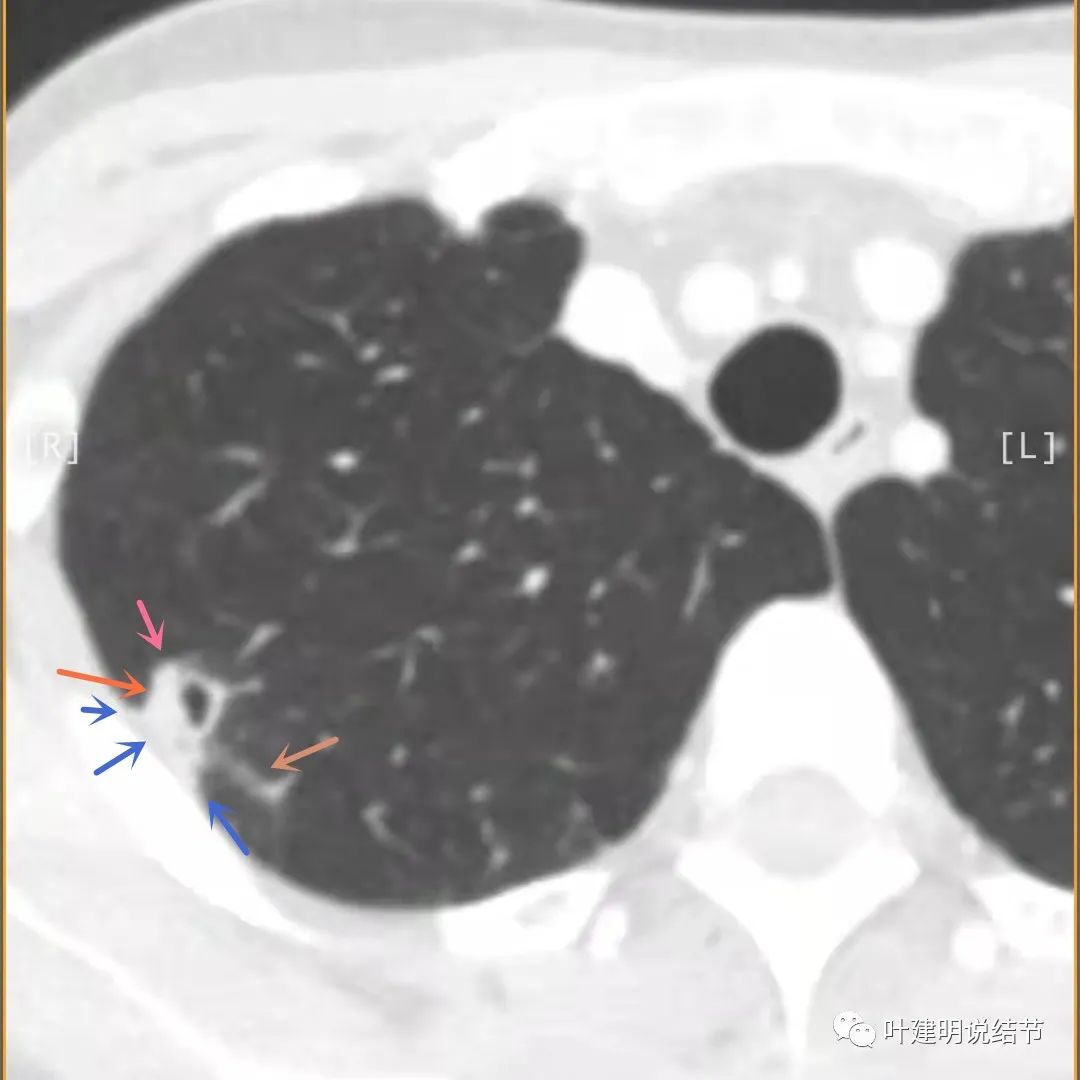

我们再来瞧瞧冠状位与矢状位的图像:

病灶较散,有磨玻璃影,但磨玻璃的边缘模糊不清(砖色箭头),囊壁密度过高(粉色箭头),毛刺样的结构偏长,空洞内壁较光滑,有卫星灶(绿色箭头)

病灶邻近胸膜增厚明显(蓝色箭头);病灶似三角形,边缘平直(桔色箭头);有磨玻璃淡且散,边缘不清(砖色箭头);有卫星病灶(绿色箭头)

有卫星灶,且条索状(绿色箭头),囊壁密度过高(粉色箭头);有空腔征(黄色箭头)

邻近胸膜增厚明显(蓝色箭头),病灶边上部分有淡磨玻璃(砖色箭头)

病灶与胸壁间不似毛刺,像炎性粘连(相连的结构粗细均匀,没有离开病灶后变细,密度较高,邻近胸膜也增厚的);有卫星状(绿色箭头);有淡且散的边缘不清的磨玻璃成分(砖色箭头)

病灶密度高,膨胀性弱,有中间空洞(黄色箭头),囊壁密度过高(粉色箭头);有淡磨玻璃成分(砖色箭头)以及邻近胸膜的明显增厚(蓝色箭头)

总体影像分析:

倾向恶性的特征:1、病灶随访增大;2、囊壁厚薄不均,局部增厚明显;3、增强有强化;4、结核相关检查除外PPD外均没有依据;5、内壁有的层面不光滑,有突起不平的地方;

倾向良性的特征:1、病灶空腔随访增大,但实性部分变化有限;2、囊壁整体密度过高,部分区域有点状高密度;3、囊壁薄的地方较为平整;4、邻近胸膜明显增厚,并也有强化,在增强片子上可见极低密度区,考虑干酪样坏死可能性大;5、主病灶强化过于明显,如果是肿瘤,生长速度应该更快;6、主病灶上方有其他慢性炎表现的病灶,从一元论角度需同源因素先考虑;7、病灶有磨玻璃成分,但磨玻璃部分密度过淡且散,与正常肺组织界限模糊;8、PPD试验强阳性,且后续沟通中其公公以及丈夫和丈夫的姐妹均有结核病史,有的有治疗,有的没有治疗。

我的意见:首先考虑炎性病变,以肉芽肿性炎伴坏死可能性为大(结核性优先考虑),可能性占7成以上;不能完全除外恶性,可能性小于2-3成;不能除外只是慢性炎症或其他炎症。建议试验性抗结核治疗4-6周后复查右上叶靶扫描加重建,再进行评估。如果病灶有所吸收好转则继续抗结核治疗;如果病灶进展,可以依诸多专家意见手术。